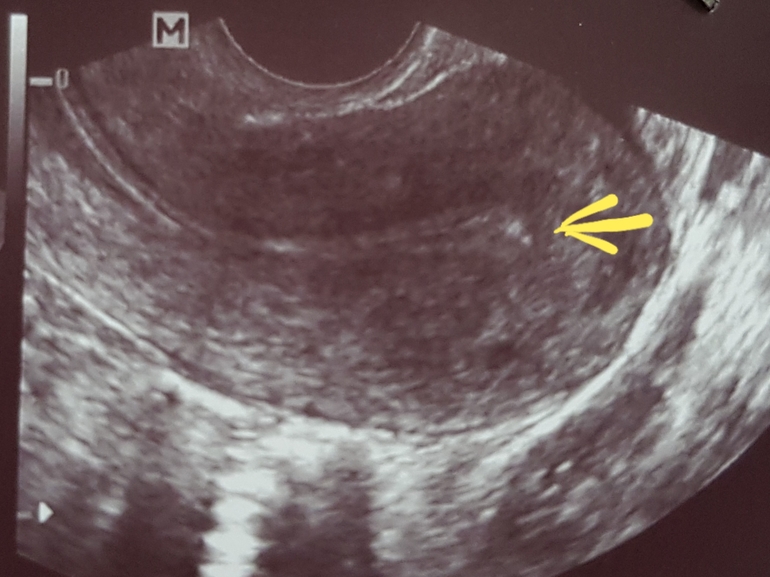

Что это может быть?

Что за включения могут быть на узи на 10 дц?

да все что угодно вплоть до НИЧЕГО :) тлько узистка может сказать и только та которая делала

Мне белым вкраплением на узи врач увидела полип эндометрия,на гистере подтвердилось

Это и воздух может быть. Я ж тоже этот вопрос лопатила несколько дней.